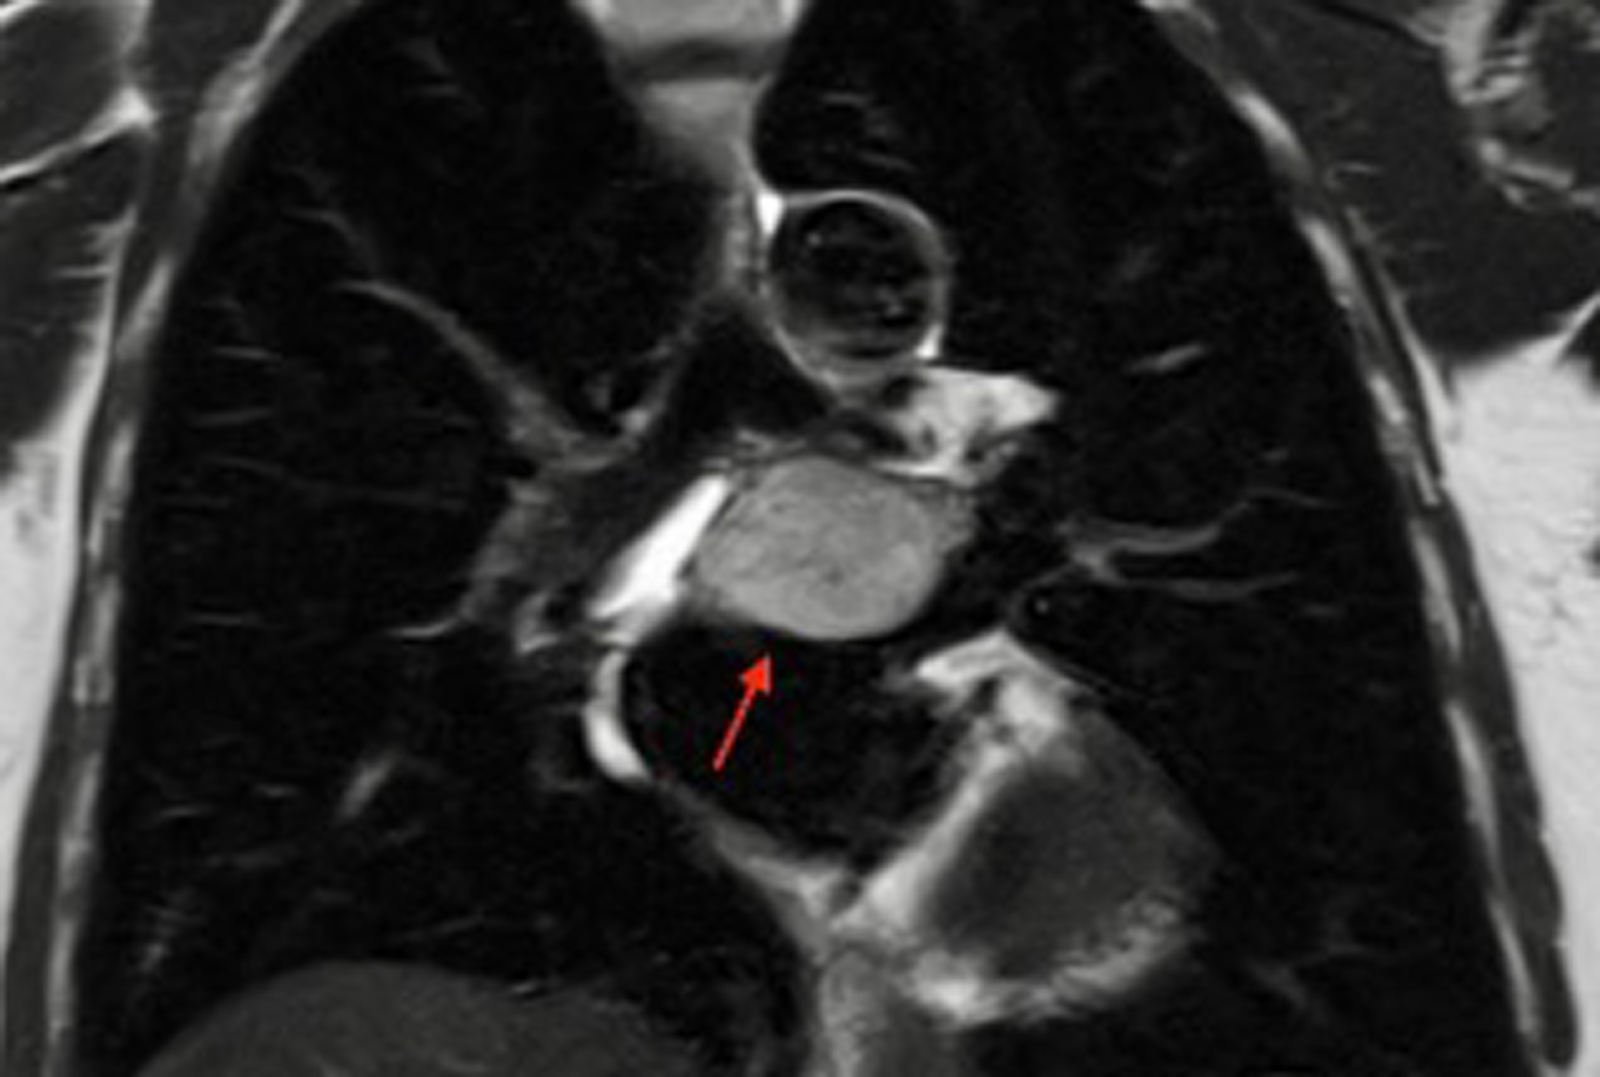

The patient presented with heart palpitations. Initial imaging revealed a large mediastinal mass above the left atrium extending into the subcarinal region with features suggestive of a paraganglioma—a rare neuroendocrine tumor that arises from extraadrenal chromaffin cells.

Upon further imaging, Dr. Bizekis confirmed attachment of the tumor to the left atrium, warranting the involvement of cardiac surgery. Coronary CT angiography also revealed external compression of the left atrium and upper pulmonary vein—further complicating the case.

Preoperative MRI revealing the tumor below the tracheal bifurcation. Source: NYU Langone Health